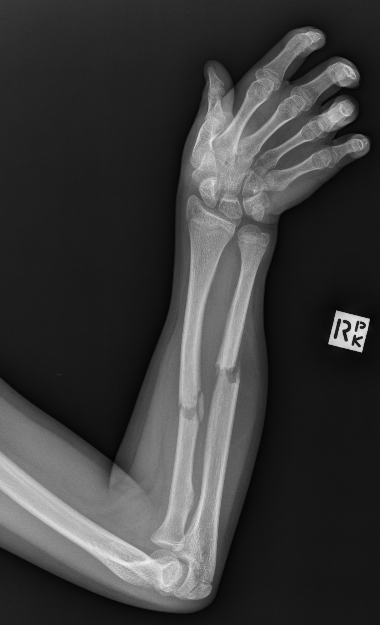

Maciej Debowski, Radiopaedia.org. From the case rID: 66146

Bascule antérieure (= fracture de Goyrand-Smith) : avis chirurgical. Immobilisation par attelle plâtrée postérieure en position neutre.

Fracture styloïde radiale plus styloïde ulnaire (fracture de Gérard Marchand) : avis chirurgical.